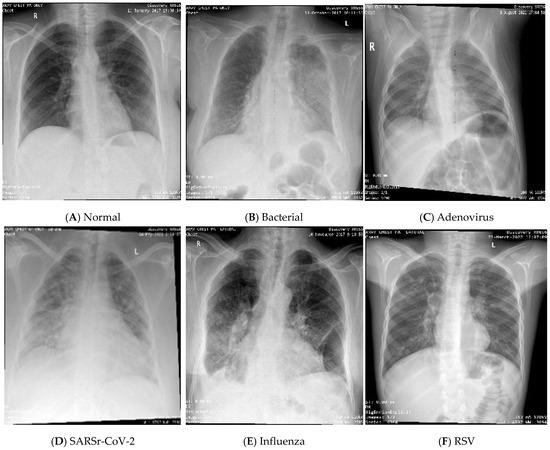

To obtain the datasets from the hospital databases, a physician gathered the required viral patients by searching for the desired test name and range of years. While there is no test for bacterial infection, the patients whose diagnosis contains the word “bacterial pneumonia” were selected as cases for the bacterial class. It is important to note that the data in the normal category were collected from a patient who was scheduled for surgery to ensure that the patient’s lungs were healthy. The CXR images from the first dataset were produced using an Optima XR240amx, General Electric Healthcare from Chicago, United States. All CXR images in datasets (I) and (II) are posterior–anterior (PA), and anterior–posterior (AP) views were included. While there were CXR images of both lateral views, the date gap between the diagnosis and obtaining the CXR images was more than 48 h, and/or those that did not have tabular data were excluded. Some samples of the dataset for different classes are shown in Figure 3. The process of obtaining IRB approval from hospitals and collecting, cleaning, and organizing the data took approximately a full year. The COVID-19 cases were collected for the patients that visited from the year 2019 to the year 2022, while the remaining cases were collected for patients from the year 2014 to the year 2023.

Figure 3.

CXR samples of the dataset.